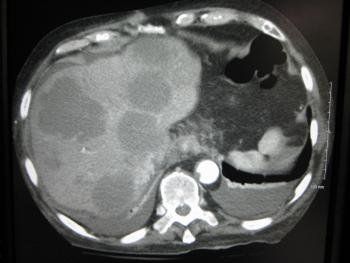

- УЗИ, КТ, МРТ;

Печень - это важнейший орган, через который проходит кровь от разных органов, поэтому нередко она становится объектом метастазирования, и таким образом здесь образуется вторичная опухоль. Своевременное выявление метастазов в печени – одна из приоритетных задача врачей-онкологов в борьбе с патологией.

Метастазами называют вторичные очаги, формирующиеся из-за попадания элементов рака из первичного, главного очага опухоли с кровью. Метастазы в печени довольно часто развиваются при 4-й стадии рака разных органов, что и становится главной характеристикой такой стадии рака.

По статистике, печень бывает поражена метастазами намного чаще, чем иные органы, – в 85% всех случаев. Когда-то распространенное мнение о том, что метастазы свидетельствуют о неизлечимости онкозаболевания, сегодня уже устарело. Благодаря достижениям современной онкологии в ведущих клиниках ряда стран с развитой медициной (США, Израиль, Швейцария и т.д.) удается провести успешное лечение метастазов печени за границей.